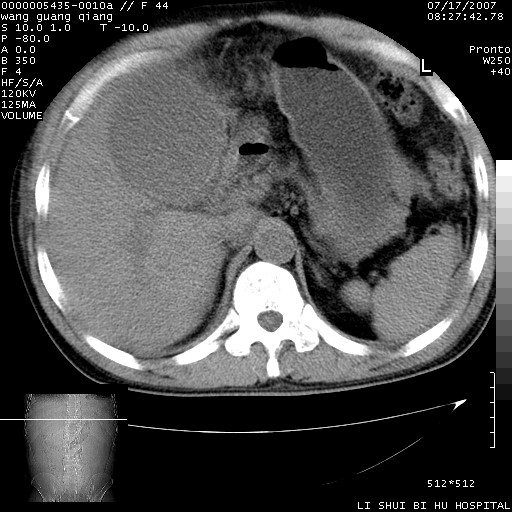

以下是引用dyqct在2007-7-18 10:46:00的发言:[br]胆囊明显增大,壁增厚,明显强化;后下方见大片高密度区,ct值68hu,无强化,周围见多数条纹状高密度影,边界不清。双膈下间隙、肝肾隐窝见带状及片状低密度区。[br]右侧胸壁后缘亦见新月形水样密度区。[br]考虑:1、急性胆囊炎伴周围出血;[br] 2、少量腹水、右侧少量胸腔积液。[br][br][本贴已被 dyqct 于 2007-7-18 10:48:47 修改过]